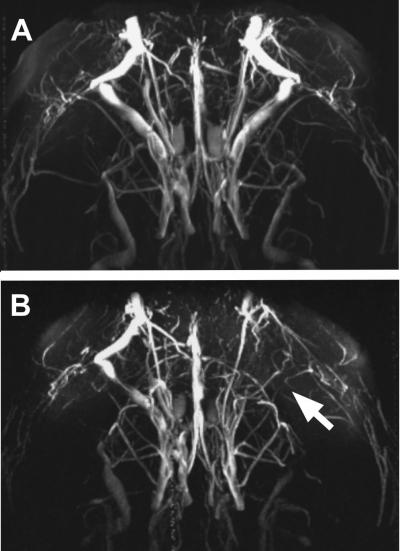

Antibodies are the defense molecules of the body's immune system against foreign invaders. If the antibodies cease to distinguish between "foreign" and "self", they attack the cells of the own body, and are thus referred to as autoantibodies. These can trigger autoimmune diseases. Using MR angiography and other methods, Marion Bimmler and her colleagues have now shown that the autoantibodies bind to specific surface proteins (alpha1 andrenergic receptors) of vascular cells and thereby damage the blood vessels of the brain. The reason: The autoantibodies generate a continual stimulation of the receptor and at the same time trigger an increase in intracellular calcium ion levels. As a result, the blood vessel walls thicken, and blood flow to the brain is disturbed.

*Antibodies to the 1-Adrenergic Receptor Cause Vascular Impairments in Rat Brain as Demonstrated by Magnetic Resonance Angiography